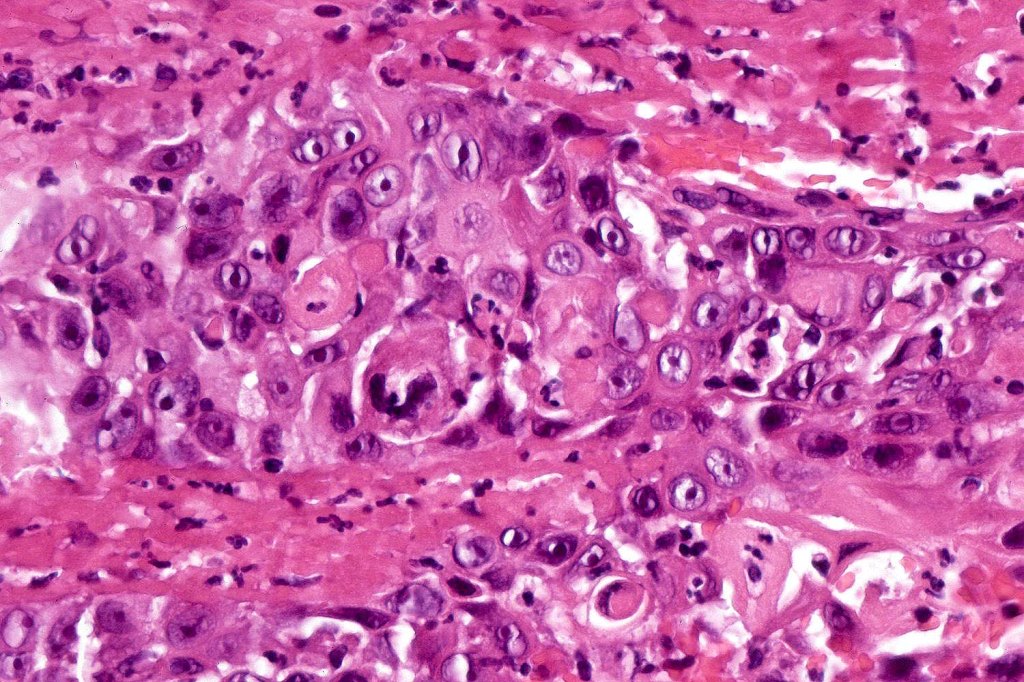

•Varying degrees of squamous differentiation- well, moderate, poorly, undifferentiated & anaplastic

. Presence of desmosomes, individual cell keratinization, keratin pearls, keratocysts

•Variable pleomorphism

•Nucleolar prominence

•Mitoses typically numerous & may be atypical